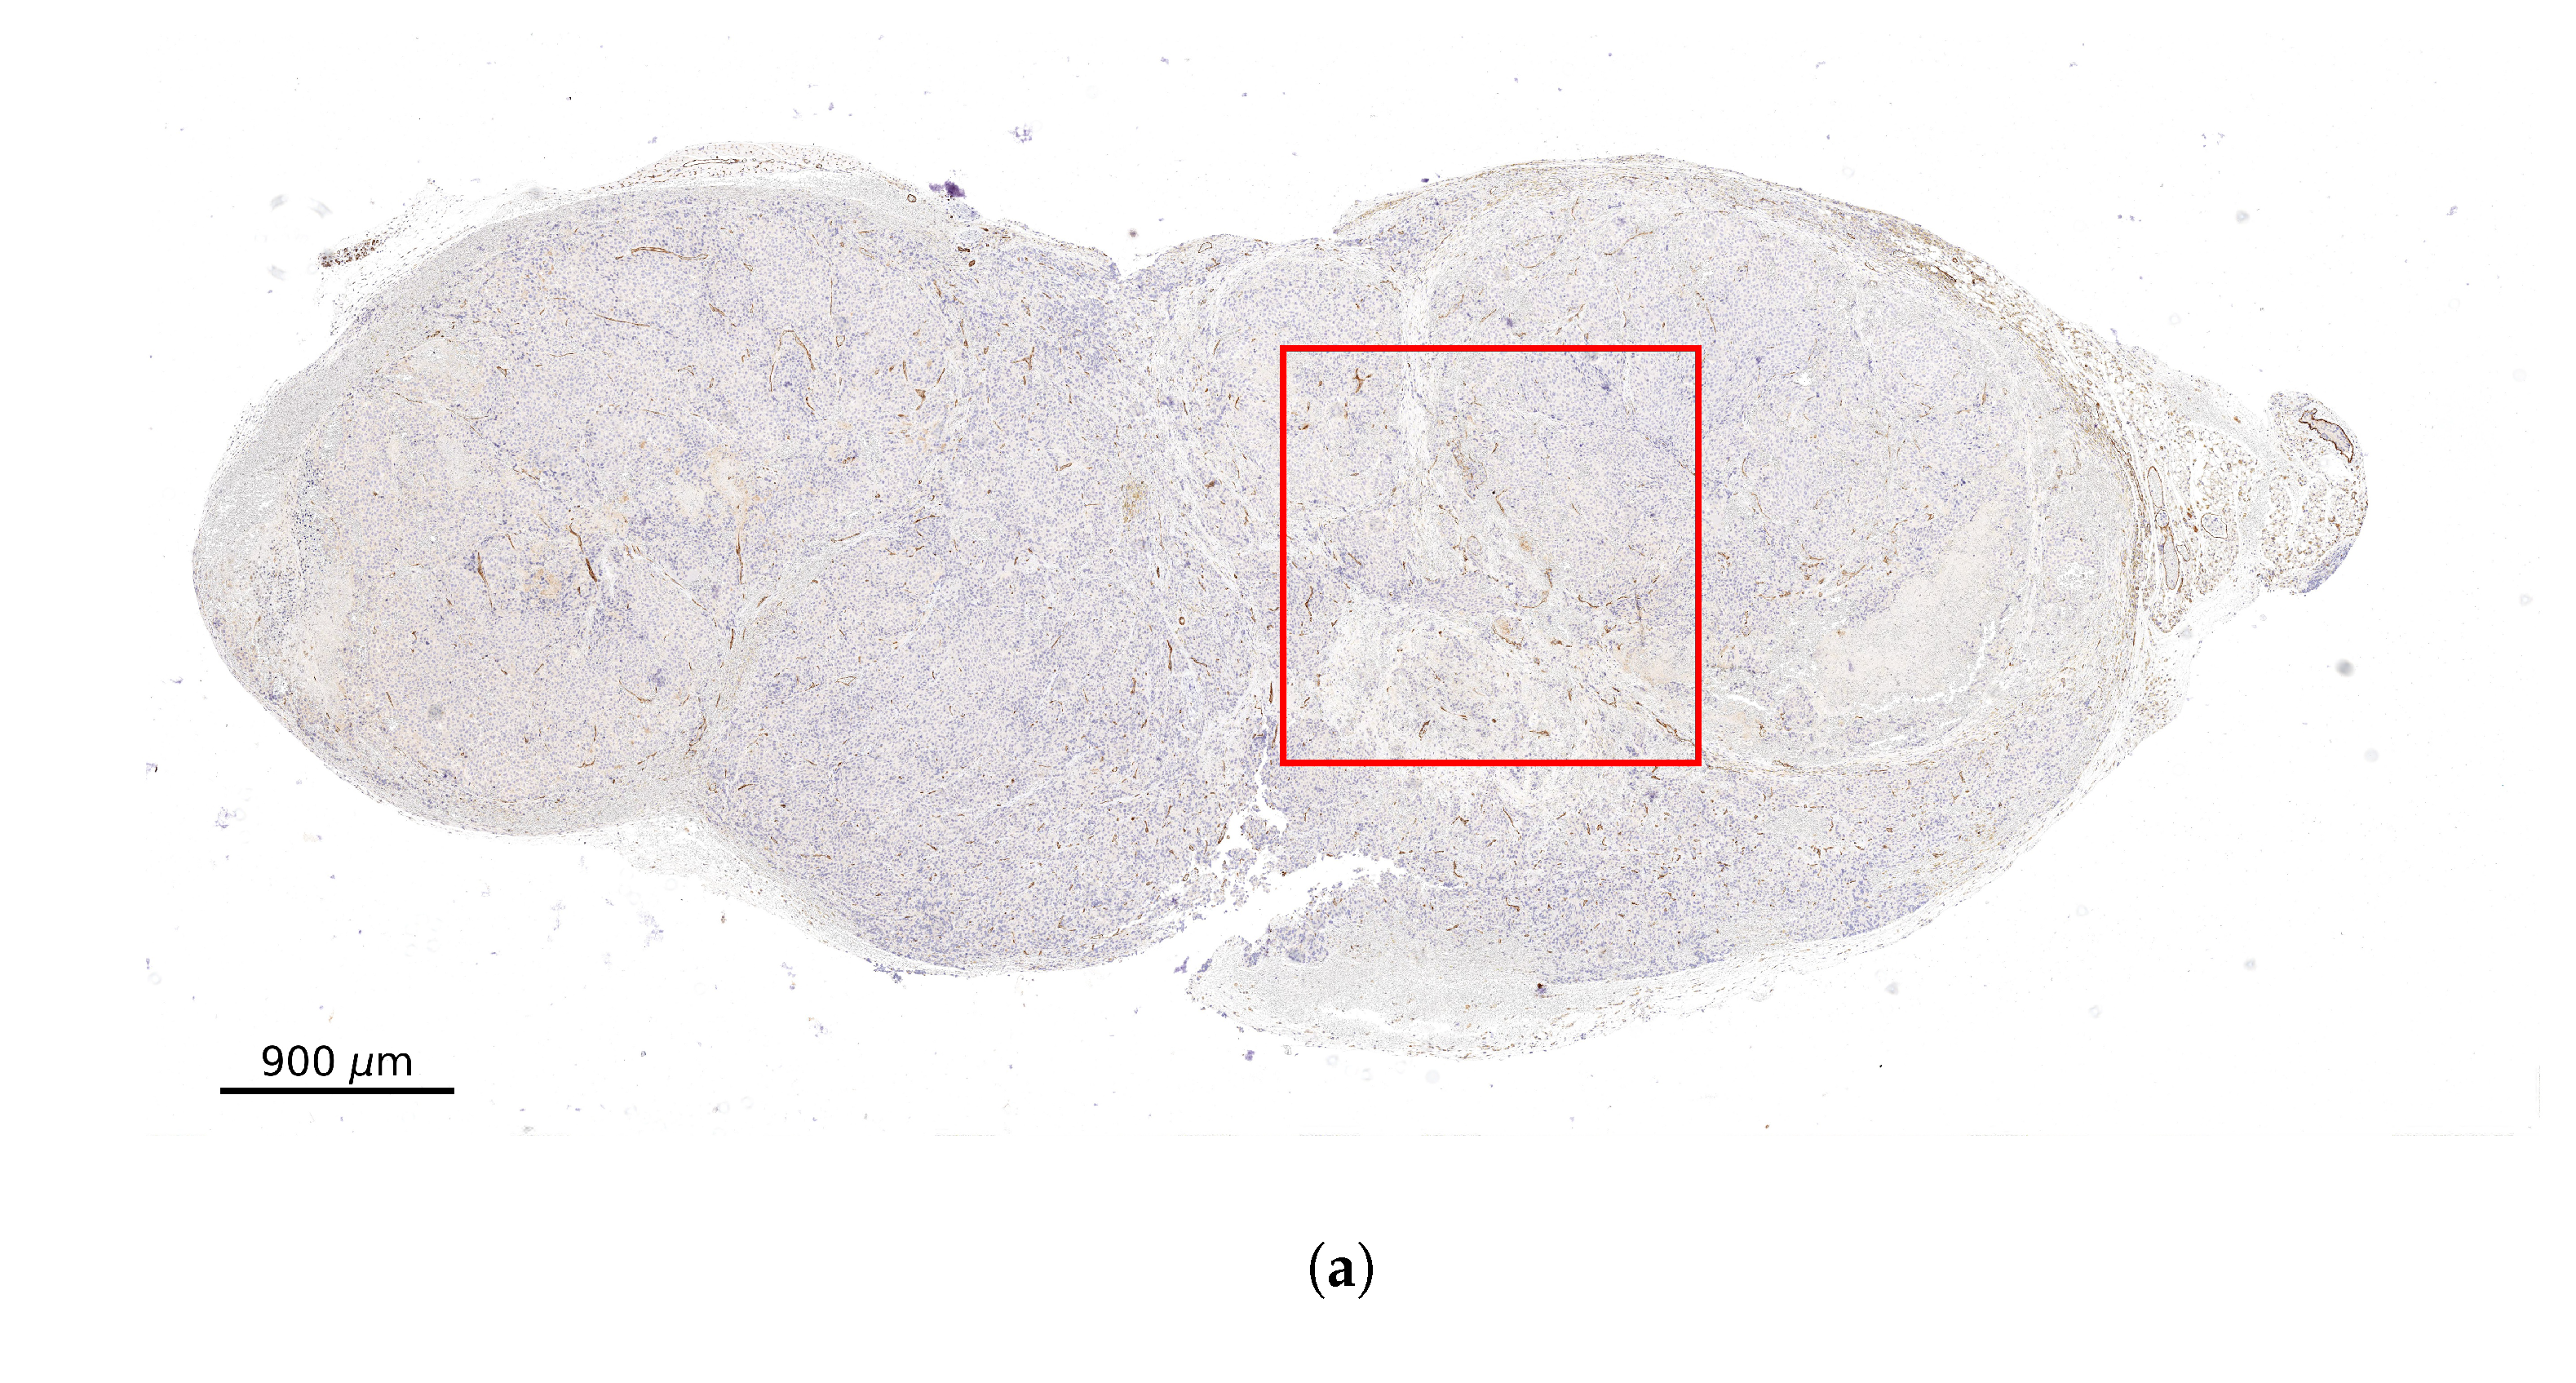

2.2. Stained Tumor Sections

2.3. Computational Domain and Vessel Map Generation